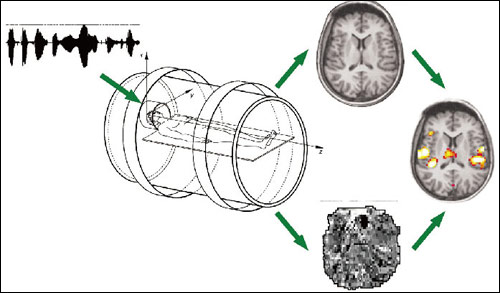

随着科技的发展,人们试图从生理学基础上解释幽默的本质和相关行为。近年来,以功能性磁共振成像(FMRI)为代表的脑认知功能成像技术得到了巨大发展,并被迅速应用到认知神经科学的各个领域。这种技术弥补了观察性研究的不足,为心理学家研究幽默提供了更丰富的视角。

功能性磁共振成像技术可以对脑的各种活动进行较为精确的了解,这为研究幽默的生理学奠定了方法基础

美国达特茅斯大学认知神经科学研究中心的科研人员以电视连续剧片段的动态生活化的实验材料进行FMRI研究,分离了幽默探测(对刺激材料的失谐之处进行探测)和幽默评价(对这种失谐的消解过程和愉悦情绪引发的过程,也包括笑的引发过程)两个认知过程,这两个过程是相分离的,与不同的脑区相关。幽默探测时,左下额叶和后颞叶出现较大的激活。而在幽默评价时尤其情绪的产生阶段,脑岛两侧和杏仁核活动增加。

综合已有的研究来看,右侧前额叶,腹内侧前额叶,颞后区以及小脑是幽默加工的重要区域,和人的自我意识有关的能力,如记忆力、逻辑推理能力、语言抽象能力、感知能力和情绪,全都汇聚在这里。